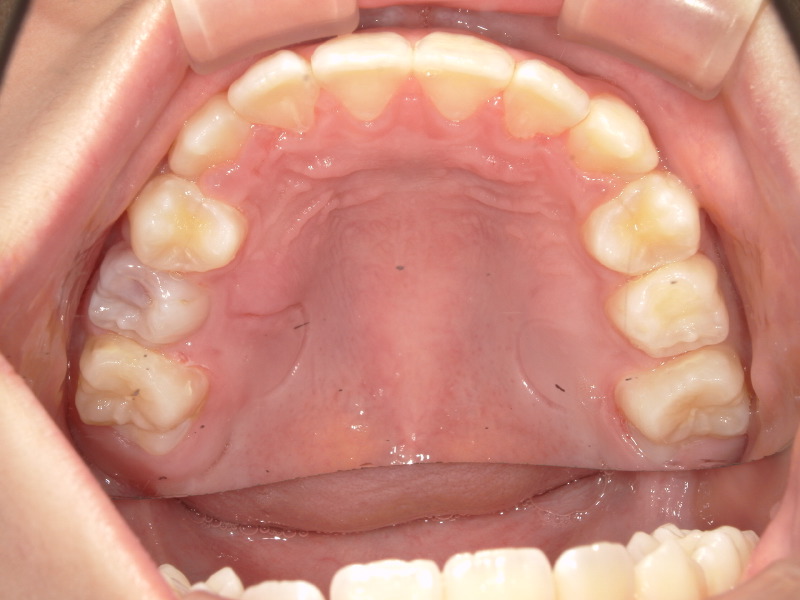

上の歯並びの変化

上の歯並びも3ヶ月後に見ると左の前から2番目の歯が綺麗に入っています。

ですが反対側の歯がまだ入りません。

でも確実に顎は大きくなってきています!